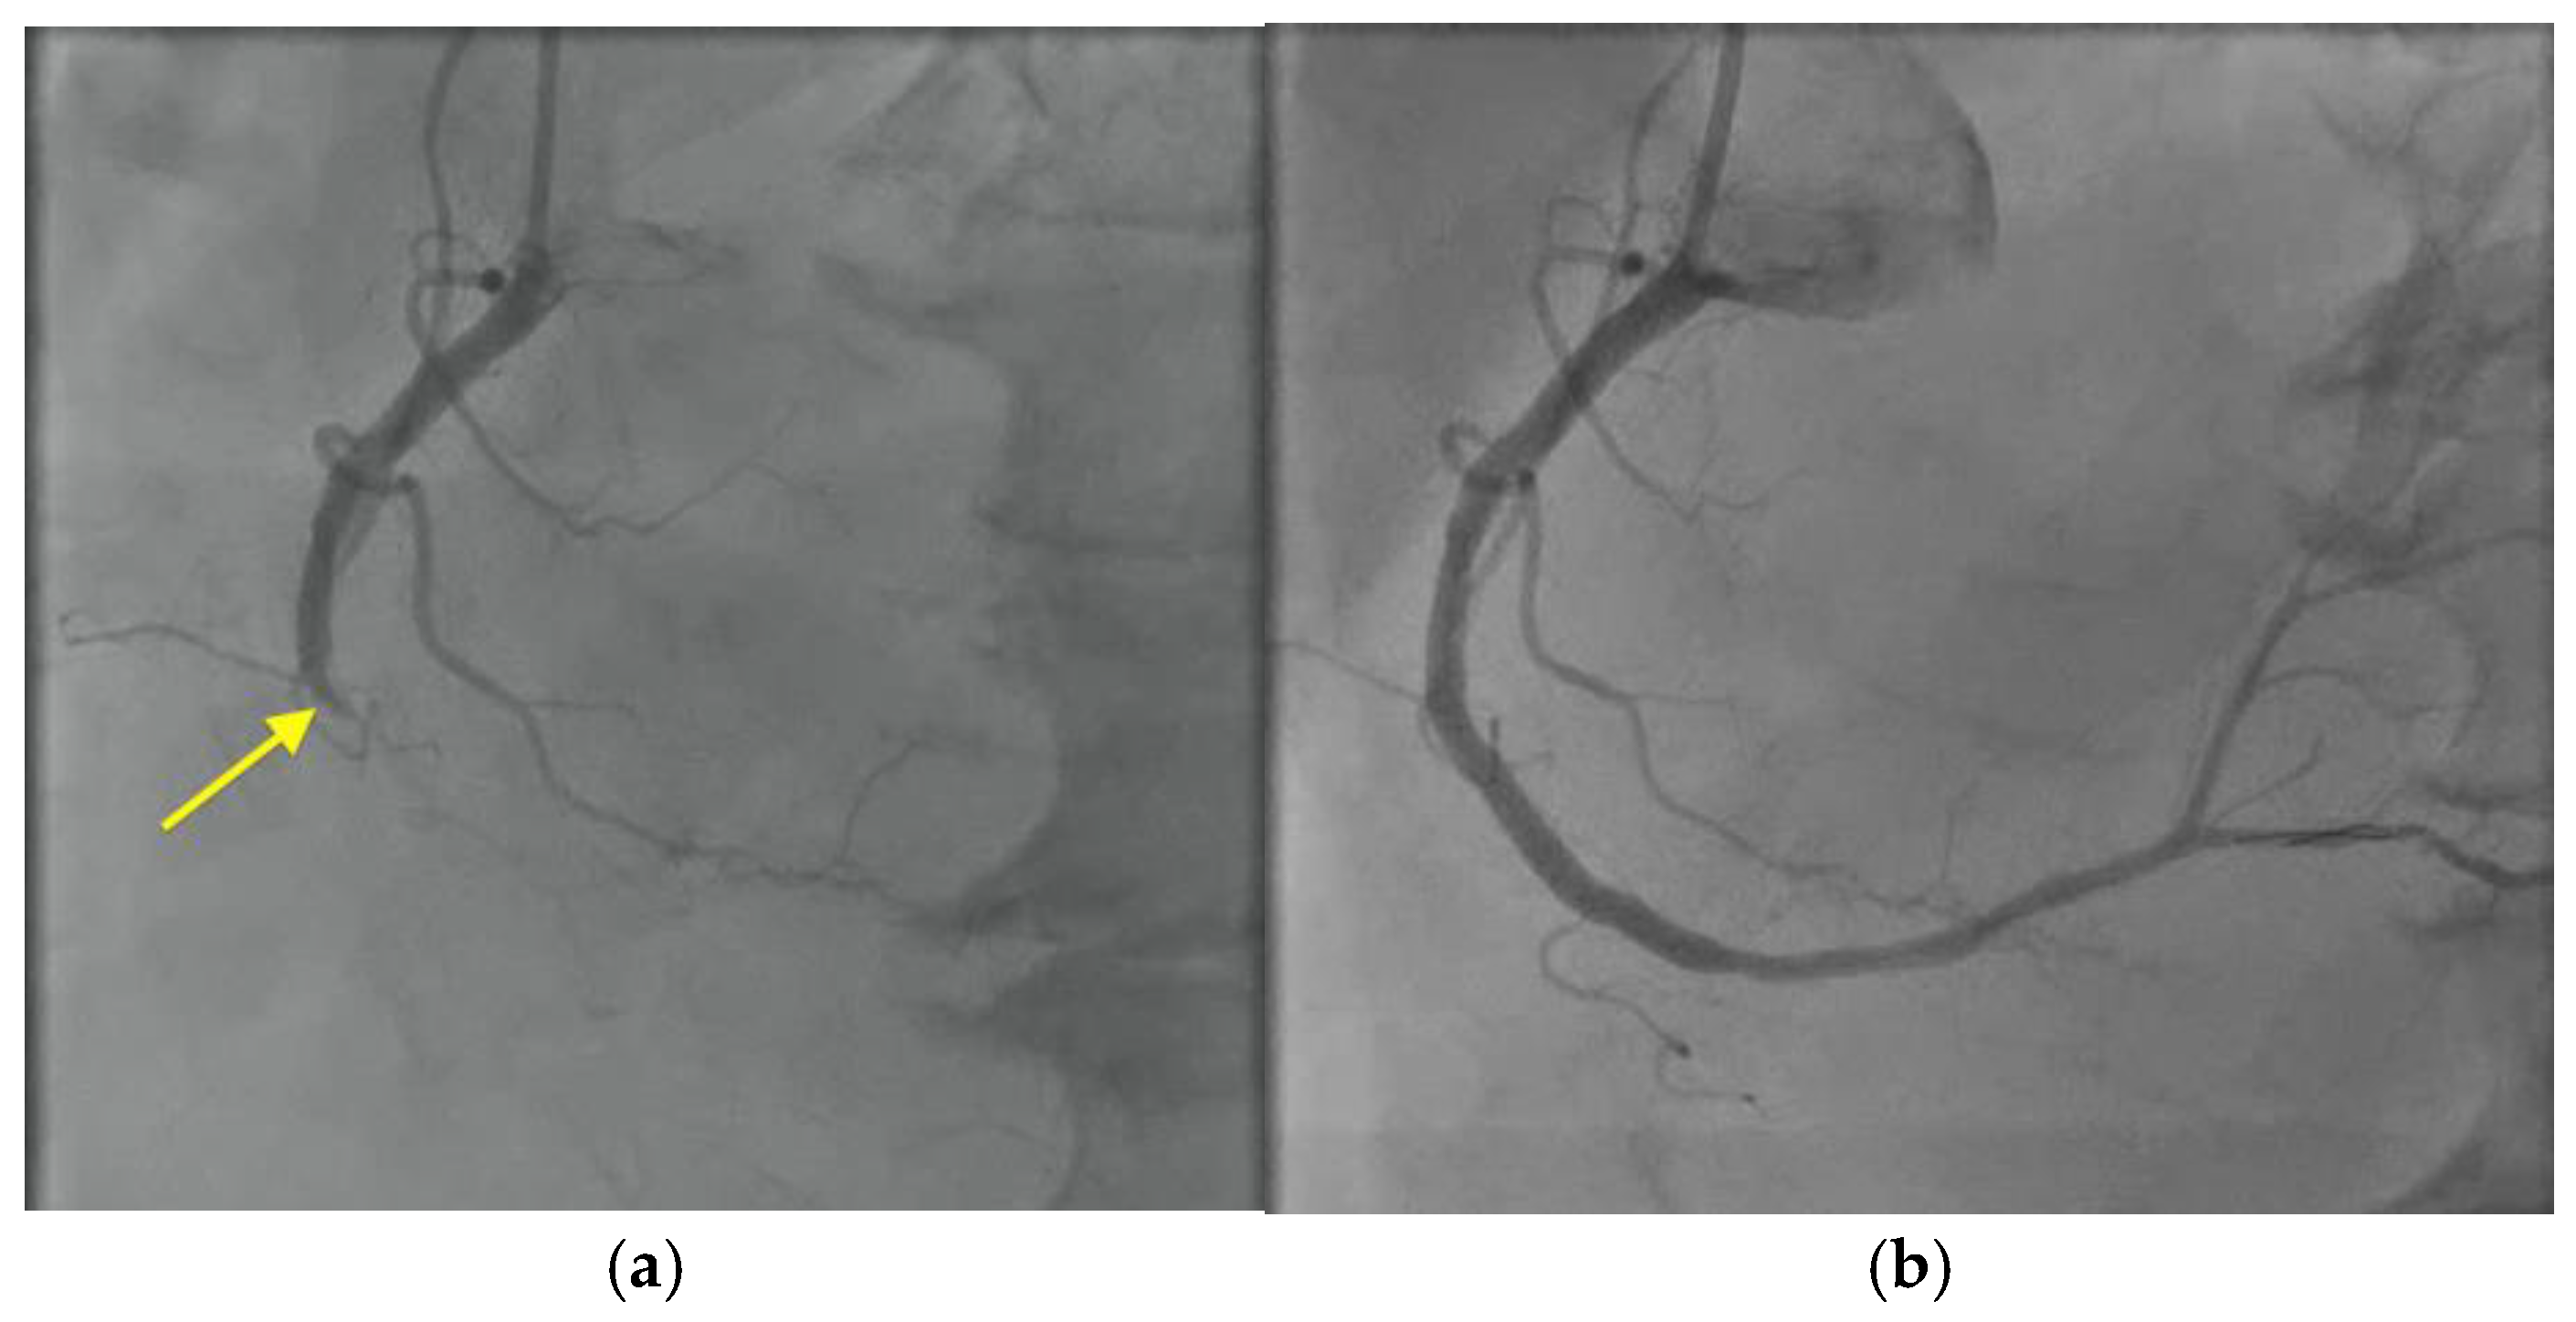

An electrocardiogram showed intermittent complete heart block and a troponin I level that was persistently elevated (1.40 ng/mL; RR < 0.08 ng/mL). Left heart catheterization revealed total occlusion of the mid-right coronary artery (Figure 6, Videos S8 and S9), and a drug-eluting stent was placed requiring dual antiplatelet therapy with resolution of the heart block. Dual antiplatelet therapy with cangrelor and aspirin was started.

Figure 6. Cardiac catheterization with right coronary artery angiogram showing: (a) total occlusion of the right coronary artery (yellow arrow), followed by (b) restoration of blood flow after deployment of a drug-eluting stent.